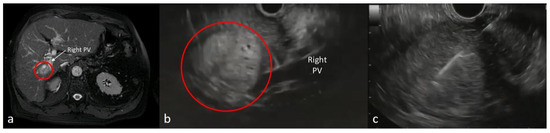

- Seo, D.-W.; Oh, D.; Hong, S.-M.; Song, T.J.; Park, D.H.; Lee, S.S.; Lee, S.K.; Kim, M.-H. Endoscopic ultrasound-guided fine-needle aspiration can target right liver mass. Endosc. Ultrasound 2017, 6, 109–115. [Google Scholar] [CrossRef] [PubMed]

| Right liver lobes | 16 (27.6) |

| Transduodenal route | 16 (27.6) |